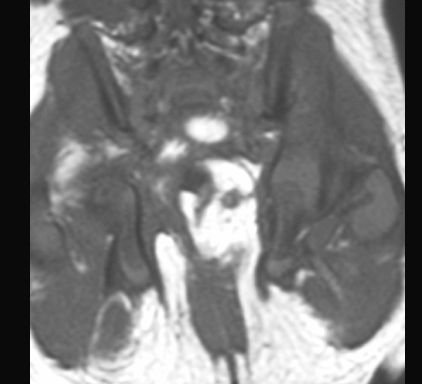

POTWORNIAK

MR